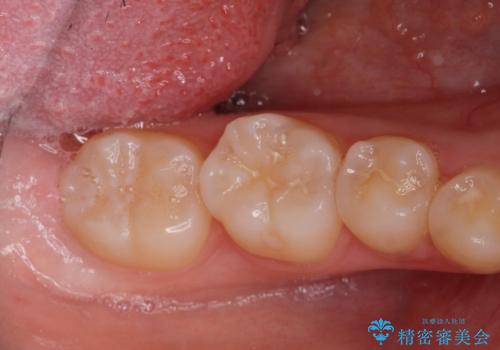

歯ぐきの形を整え、外れにくい被せ物を装着

歯の高さを出すための親知らず抜歯と歯肉切除

担当医 岡田康成